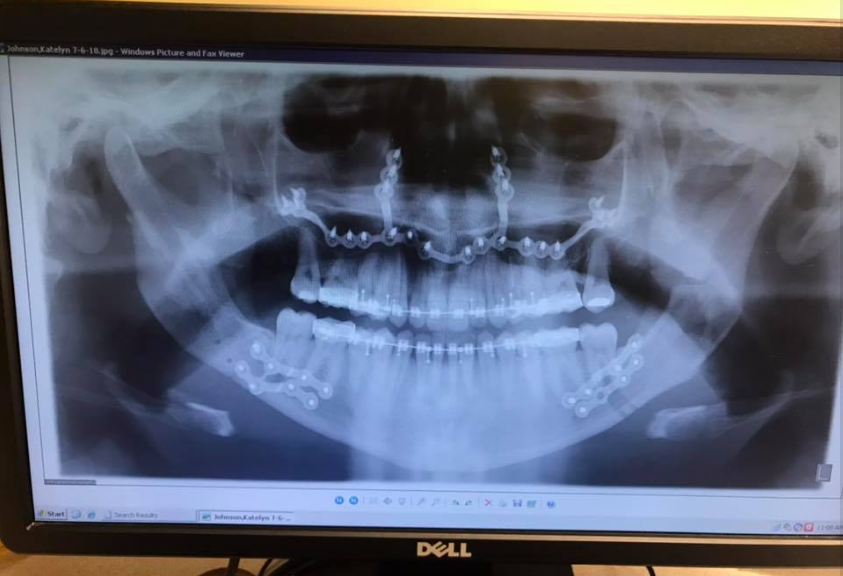

Radiografía de Katie Wolferding, fechada en junio de 2019 | Fuente: Facebook/katiewolferding